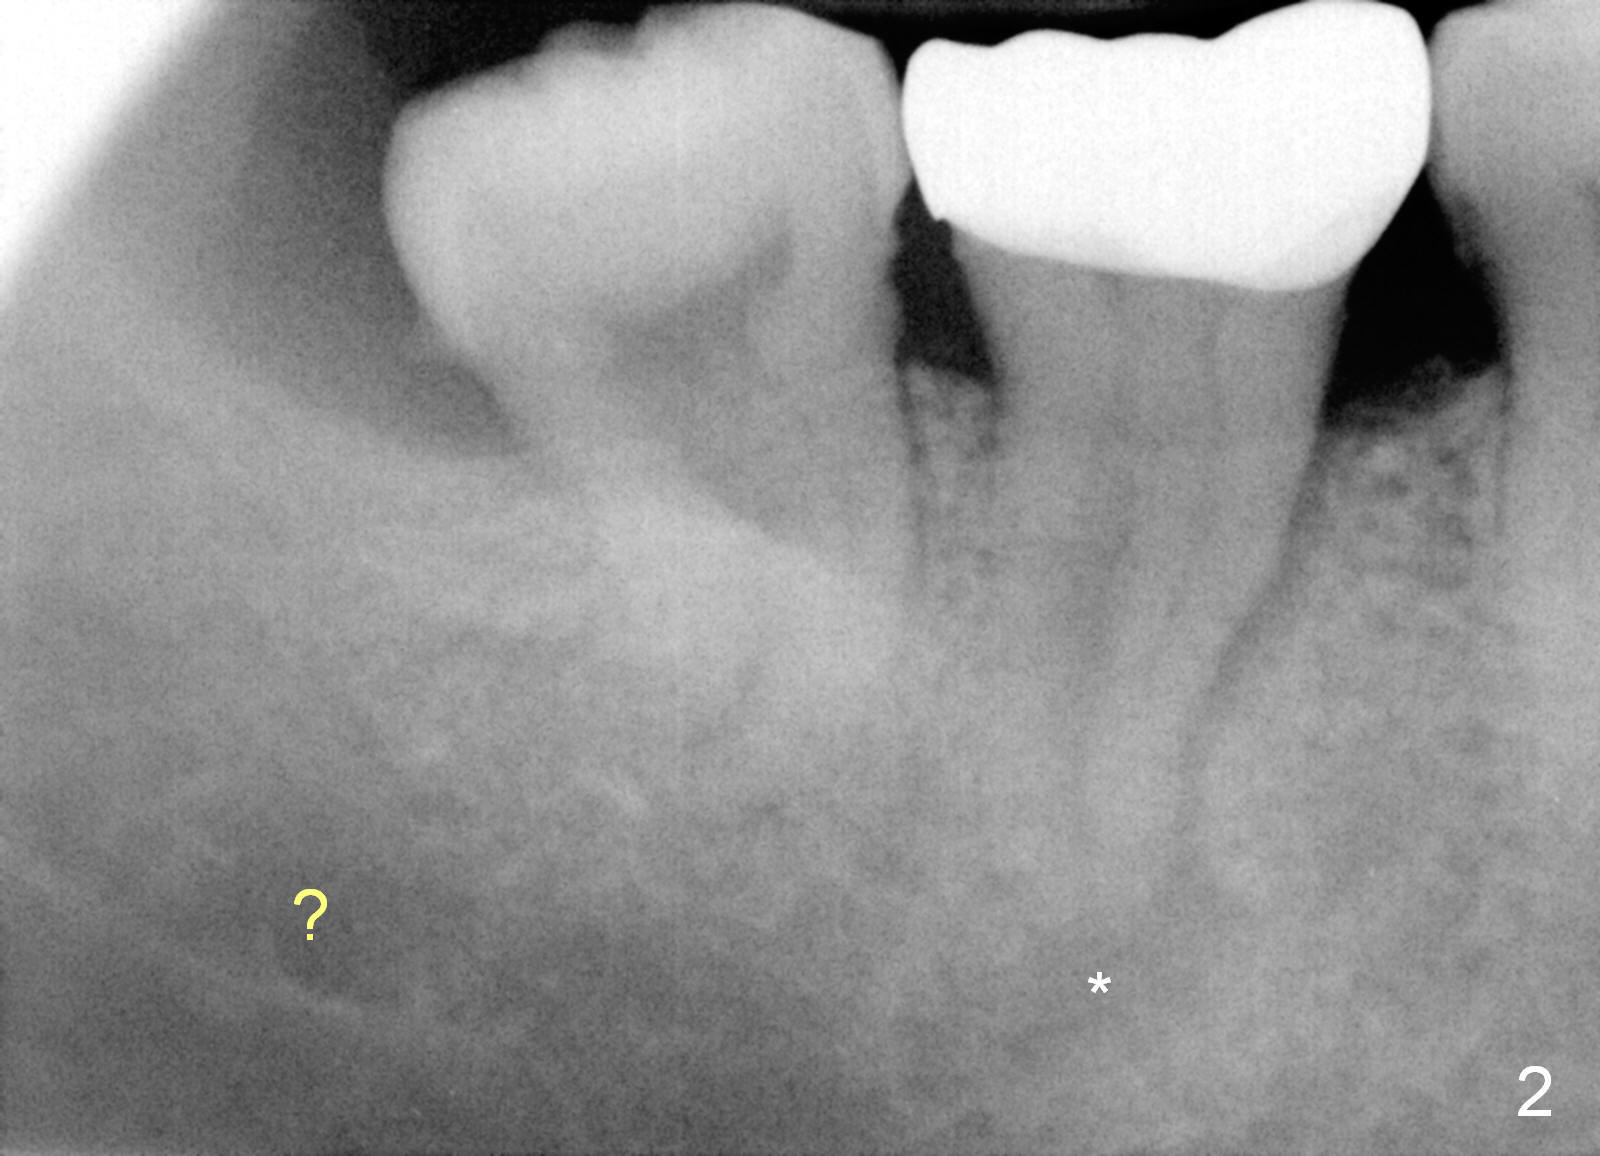

A 69-year-old lady has pain at #31. Because of curved and obliterated root canals (Fig.1,2), it is the better to extract the tooth and have an immediate implant. The roots are also long and narrow and close to the Inferior Alveolar Canal (Fig.1 yellow dashed line), whereas the canal is hardly recognizable in a 2nd PA (Fig.2 ?). For safety, taps are to be used for osteotomy (Fig.3).

She is taking a blood thinner. Make sure that she has stopped taking it for 2-3 days prior to surgery. Postop, suture and perio dressing may be needed for hemostasis. Gauze (3-4 pieces) is provided to the patient. Is a drill not used at all?